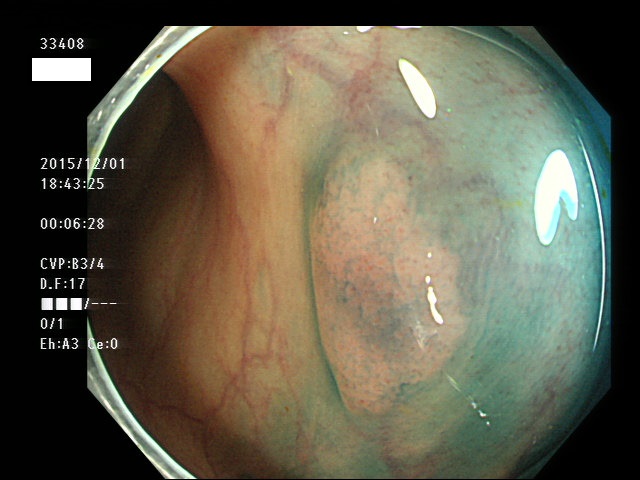

上記100名より抽出した平坦・陥凹型腺腫(=癌化の危険が高いが見落としやすい病変)の内視鏡写真